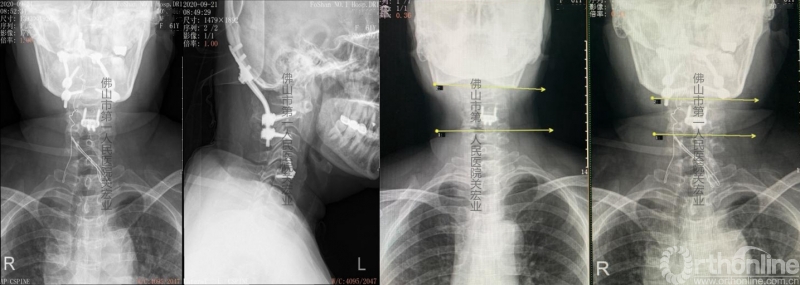

术前放射检查

影像学术前、术后对比

A:术后颈后、枕部向头顶的放射痛明显缓解。左上肢肌力提高一级,双侧下肢本体感觉改善。术前寰枢椎旋转脱位、下颌偏歪、齿状突上移、脊髓向右侧偏移的情况,术后影像学可见均有明显改善。